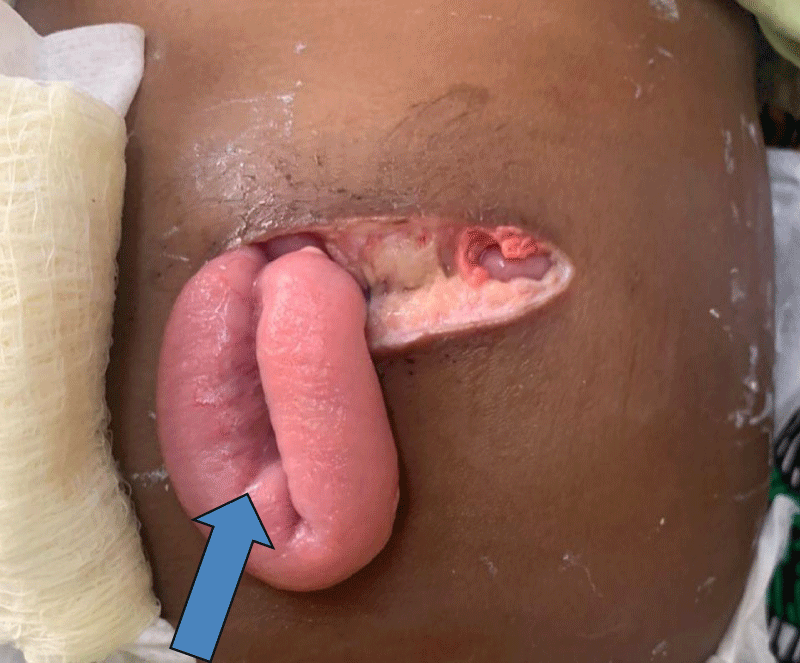

Postoperatively, the child’s recovery was complicated by delayed wound healing and subsequent wound dehiscence (Figure 2). On the ninth day after surgery, the surgical wound showed signs of poor healing, and a small portion of the incision broke down completely leading to a small bowel protruding from the surgical site. Although infection was considered, no overt signs of purulent drainage or systemic infection were noted. The dehiscent wound was closed in layers, with non-absorbable skin sutures, by a surgical resident, and daily dressing changes, along with close monitoring for infection were initiated. The patient was continued on intravenous antibiotics as a precaution and nutritional support was adjusted with enteral feeds as tolerated. Despite the resolution of respiratory symptoms, the child’s bowel was again noted to be protruding from the surgical wound by the fifteenth day, and the dehiscent wound was closed again. This time absorbable sutures were used for the thin and retracted muscle layer, and non-absorbable mass closure sutures were used for the muscle/fat/skin.

Figure 2: Protruding small bowel from the surgical wound due to full-thickness wound dehiscence (arrow).